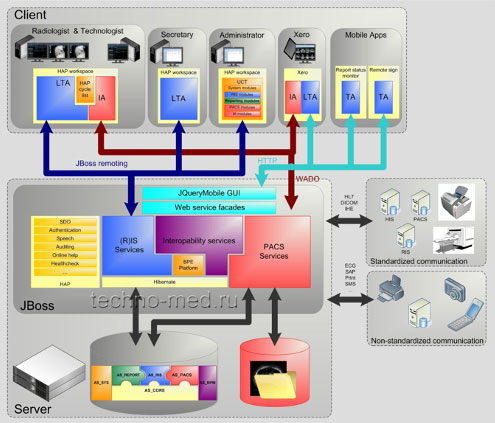

AGFA IMPAX Agility - это не просто PACS-машина. Это гораздо больше. Это платформа, которая объединяет в себе многие из программных продуктов. Это не только снижает количество лицензий, но и упрощает работу системы.

IMPAX Agility представляет собой решение для управления медицинскими изображениями, которое

- Поддерживает непрерывный поток операций с изображениями во всех подразделениях предприятия;

- Обеспечивает действие механизма реализации рабочих процессов, основанных на поставленных задачах, соответствующий современным сложным требованиям;

- Имеет минимальную совокупную стоимость владения благодаря использованию современных ИТ и единой базы данных;